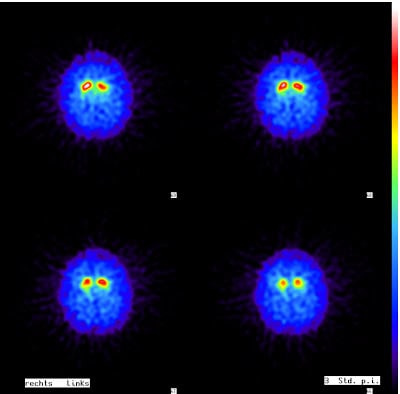

Parkinson-Erkrankungen und Parkinson-Syndrome (z.B. eine Multisystematrophie, MSA) können sehr empfindlich mittels eines DaTScans nachgewiesen werden.

Drei bis sechs Stunden nach Injektion einer schwach radioaktiven Untersuchungssubstanz werden Bilder angefertigt, die in der Regel direkt eindeutige Aussagen liefern.

Besteht anschließend noch Unklarheit, ob ein M. Parkinson oder ein Parkinson-Syndrom vorliegt, so ist die Unterscheidung mittels MIBG-Szintigraphie möglich, weil der M. Parkinson zu einer verminderten MIBG-Darstellung des Herzens führt.

Mittels DaTScan kann auch eine Levy-Body-Demenz (DLB) nachgewiesen werden, eine Parkinson-verwandte Erkrankung, bei der die geistigen Beeinträchtigungen noch vor den motorischen Störungen auftreten. Andere Demenzformen, wie die Demenz vom Alzheimer-Typ und die frontotemporale Lobärdegeneration (M. Pick), lassen sich bereits im Stadium des Mild Cognitive Impairments (MCI) erkennen. Die hierbei vorhandenen leichten kognitiven Störungen äußern sich durch Gedächtnisstörungen, Lernschwierigkeiten, Konzentrationsstörungen und schnelle geistige Ermüdung. Mittels Hirnperfusionsszintigraphie lassen sich bei den betroffenen Personen mit Alzheimer oder Pick-Demenz typische Durchblutungsstörungen nachweisen.